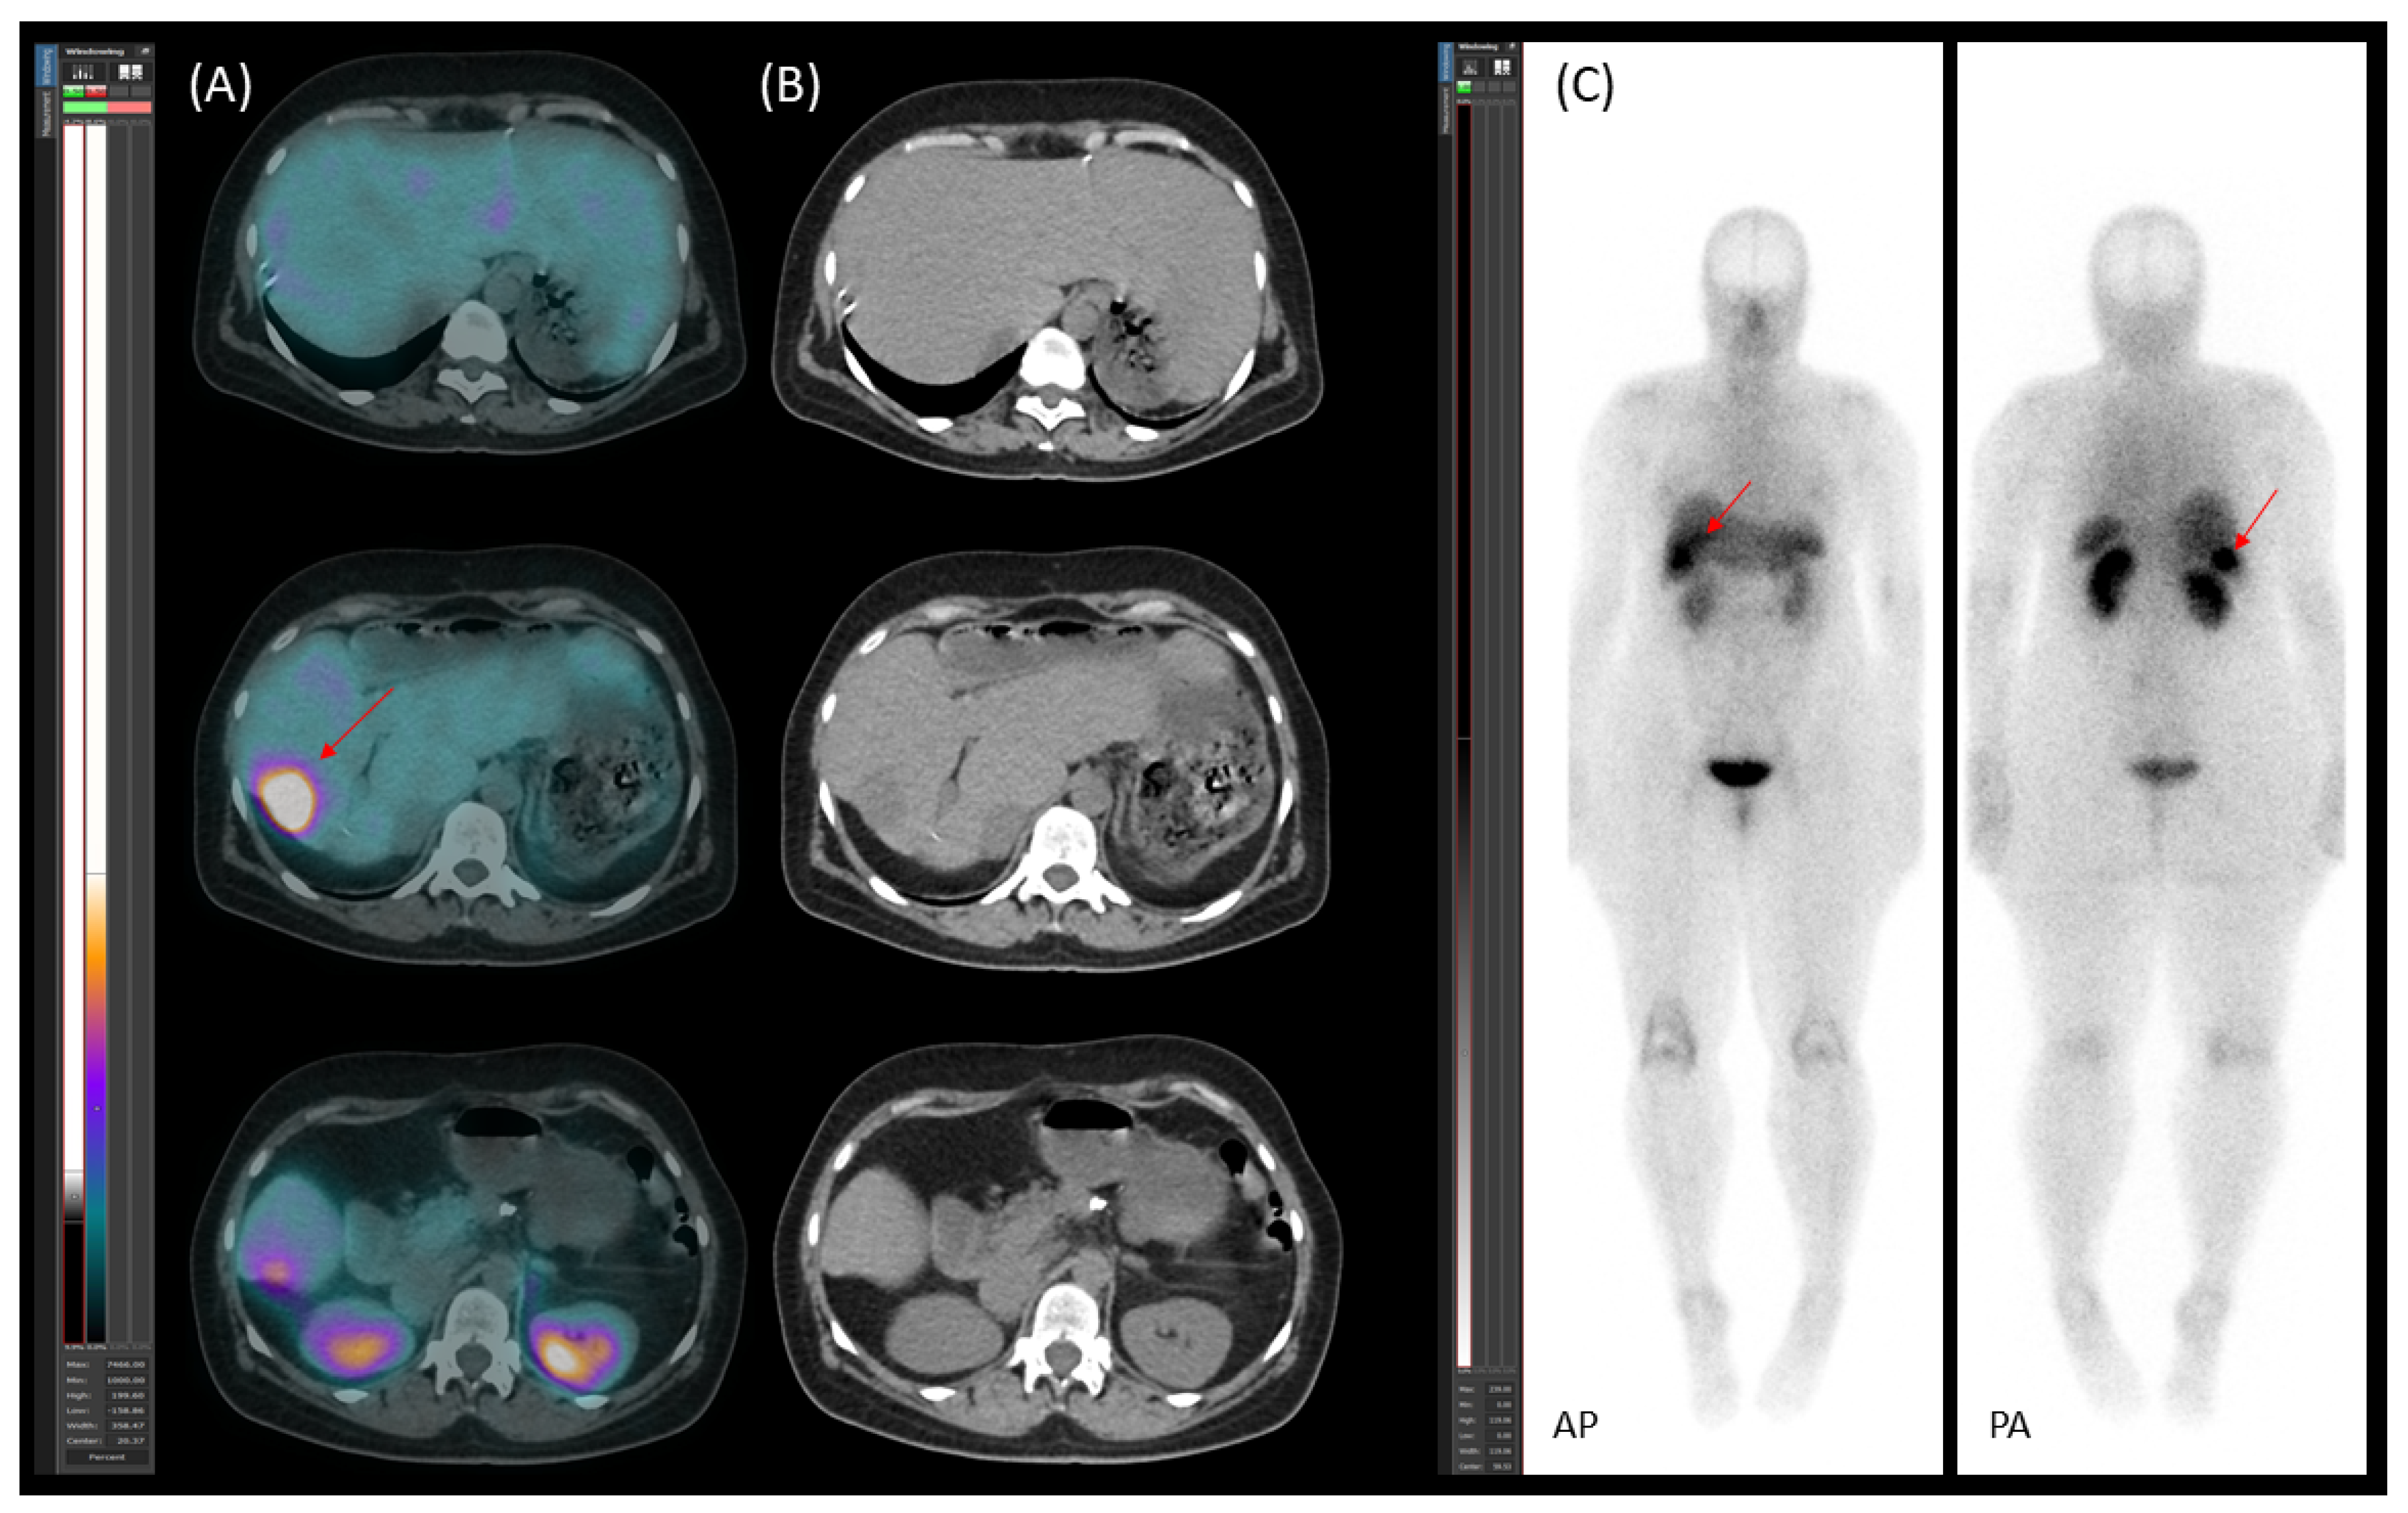

2.4. Follow-Up, Disease Progression, and Treatment

3.3.5. Disease Monitoring